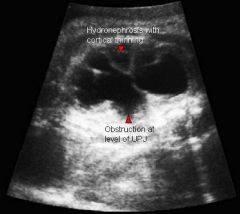

What is UPJ?

uritopelvis junction

hydronephrosis

What is hydronephrosis usually caused by?

UPJ or UVJ obstruction

What is a UPJ obstruction caused by?

bend or kink in ureter

What is hydronephrosis?

Dilation of the renal pelvis due to blockage

What is ureteropelvic junction obstruction?

Obstruction of the urinary outflow. Can be acquired or congenital.

obstruction at the confluence of the kidney and the ureter

What is the most common cause of hydronephrosis in neonates?

UPJ obstruction

What is the sonographic appearance of ureteropelvic junction obstruction?

will often show a dilated renal pelvis

Doppler: Kidney w/higher resistive indices

hyperechoic kidneys